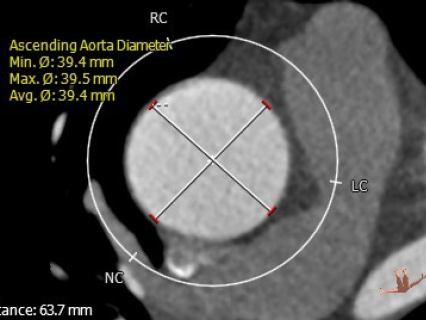

升主动脉直径:63.7mm

瓣环直径:29.1mm

瓣上4.8mm处直径:30mm

主动脉与左心室夹角:127°

主动脉瓣环平面水平夹角:60°

左冠高度:18.5mm

右冠高度:24.4mm

左室流出道直径:29.8mm

窦部直径:40.5/39.8/41.8mm

窦管交界处直径:29.7mm